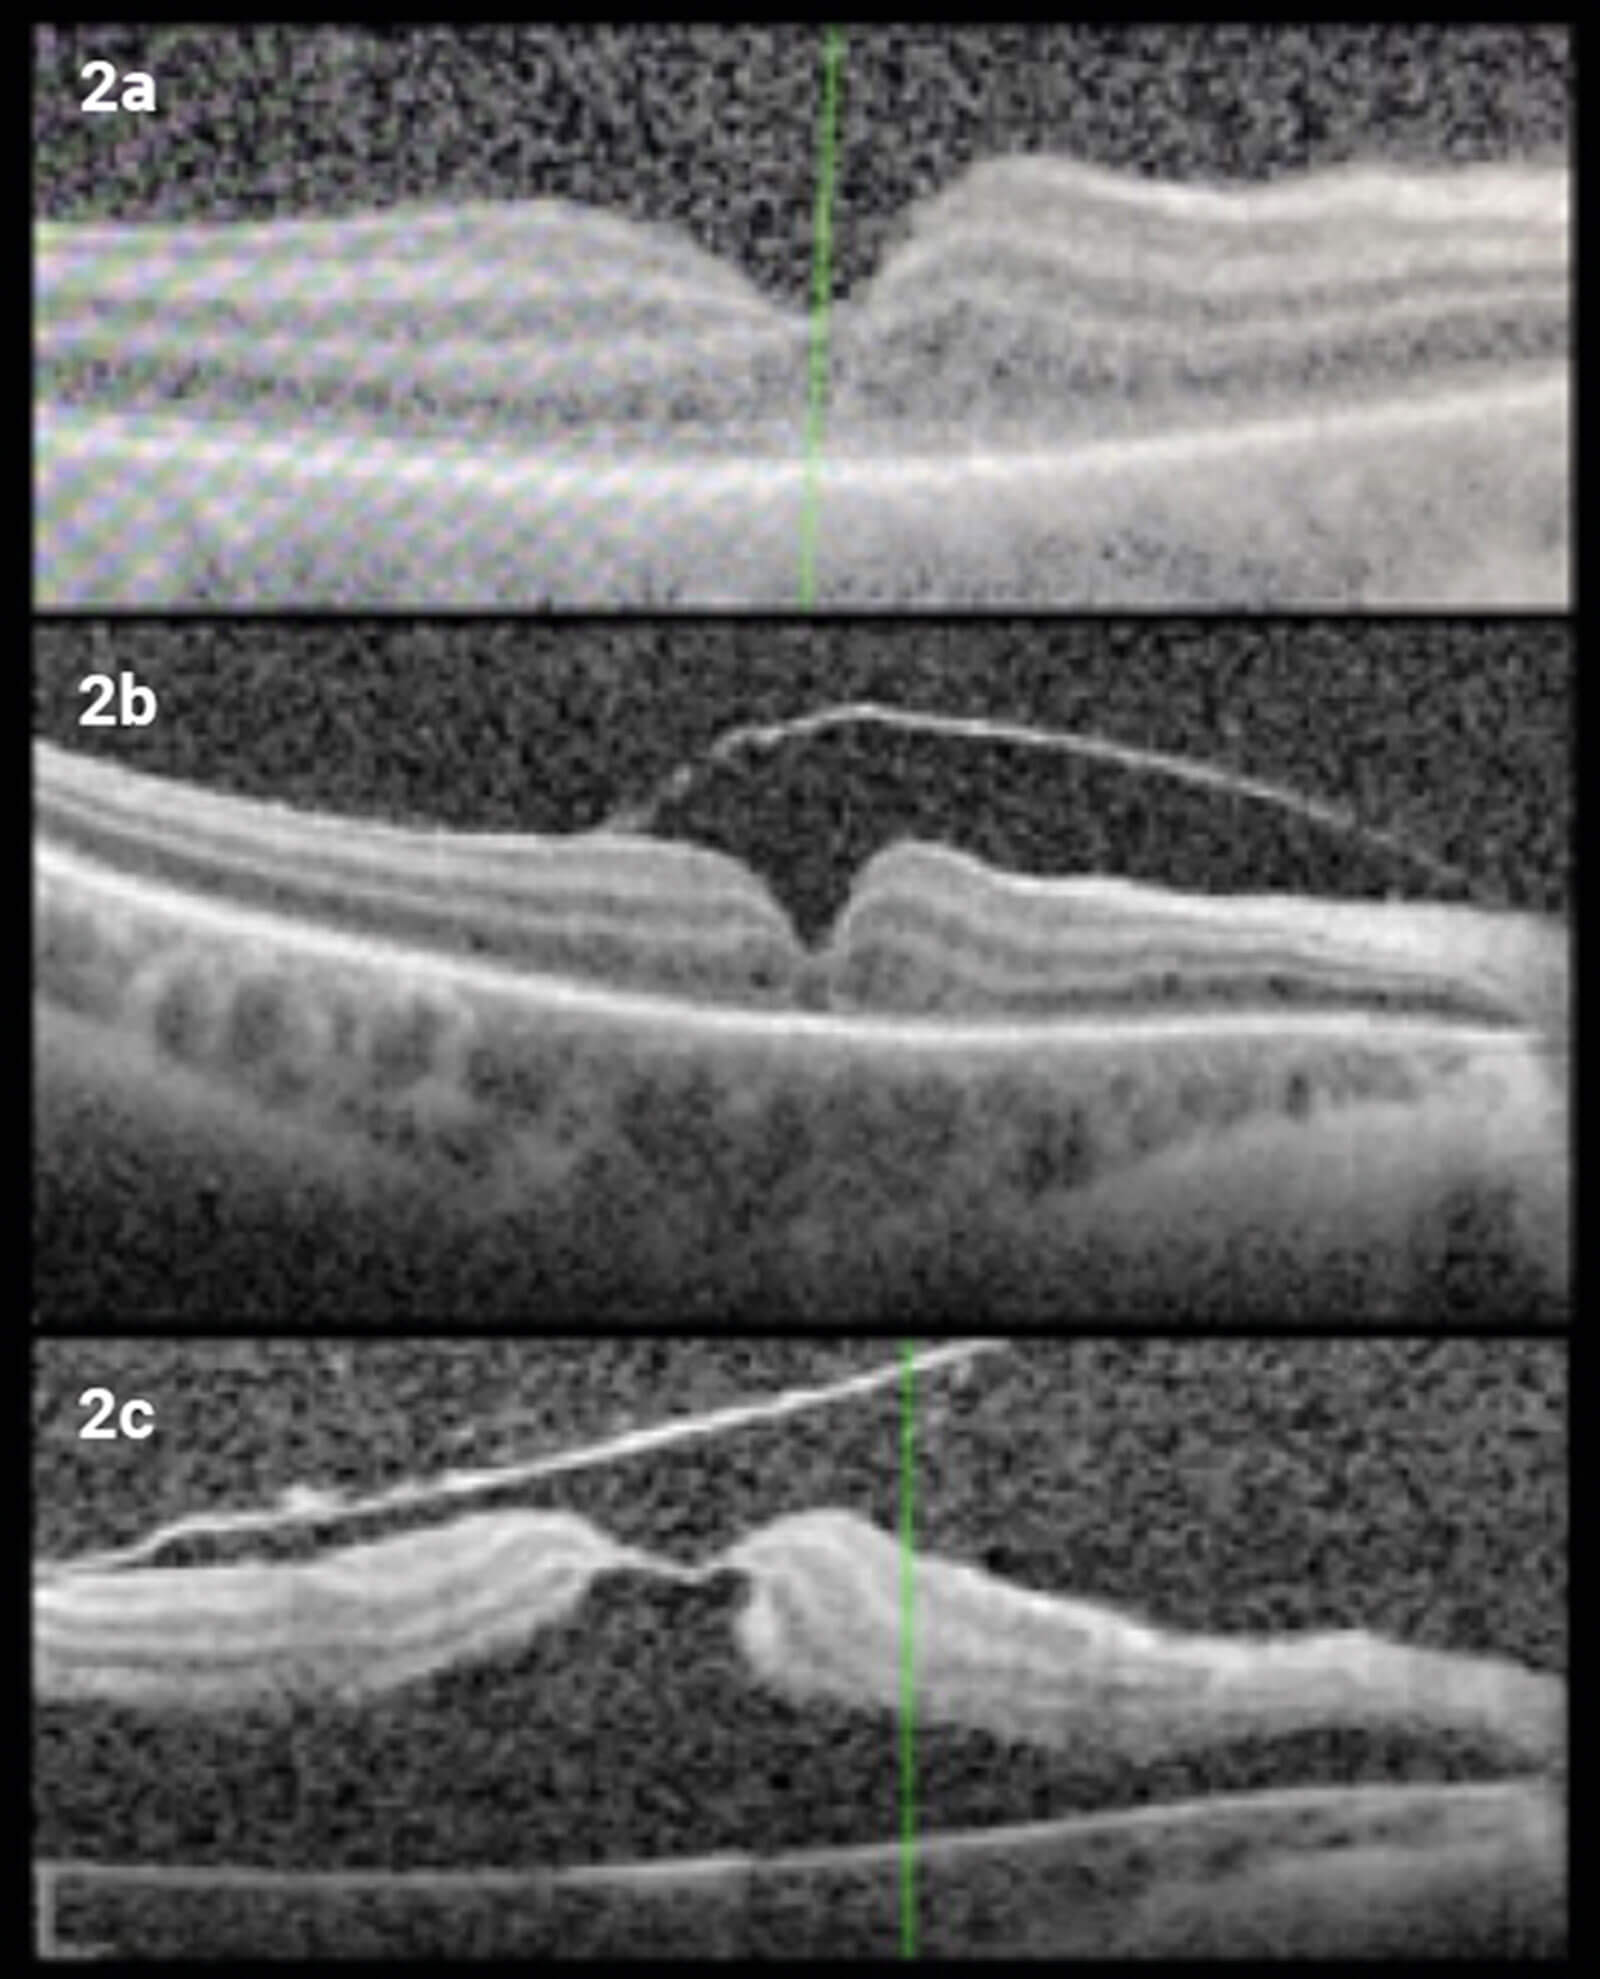

Optical coherence tomography (OCT) scan of the right macula showed hyporeflectivity of the ganglion cell layer (GCL) with relative increase in reflectivity of both plexiform layers. The GCL thickness map showed significant thinning when compared to the unaffected left eye (Figure 2a).

Figure 2: From top to bottom, OCT macula of the right eye: (2a) showing hyporeflectivity of the GCL and relative increase of reflectivity of the plexiform layers; (2b) one week later, showing development of partial PVD; and (2c) one month later, showing macular detachment and macular hole with only a thin roof of internal limiting membrane.

One week later, OCT started showing right partial posterior vitreous detachment (PVD) (Figure 2b).

One month following the electric shock, the patient developed right rhegmatogenous retinal detachment and macular hole and was listed for repair with the vitreoretinal team (Figure 2c).